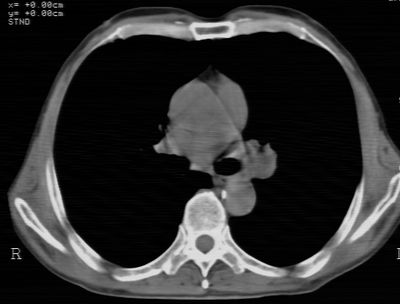

标题: CT24783:m71,既往肺心病史3年,现咳嗽,憋喘。 [打印本页]

标题: CT24783:m71,既往肺心病史3年,现咳嗽,憋喘。

1、左肺上叶spn,毛刺+分叶+血管集束征,考虑周围型肺癌可能性大

2、全小叶性肺气肿。

1)左肺上叶周围型肺癌可能。2)两肺全小叶型肺气肿。